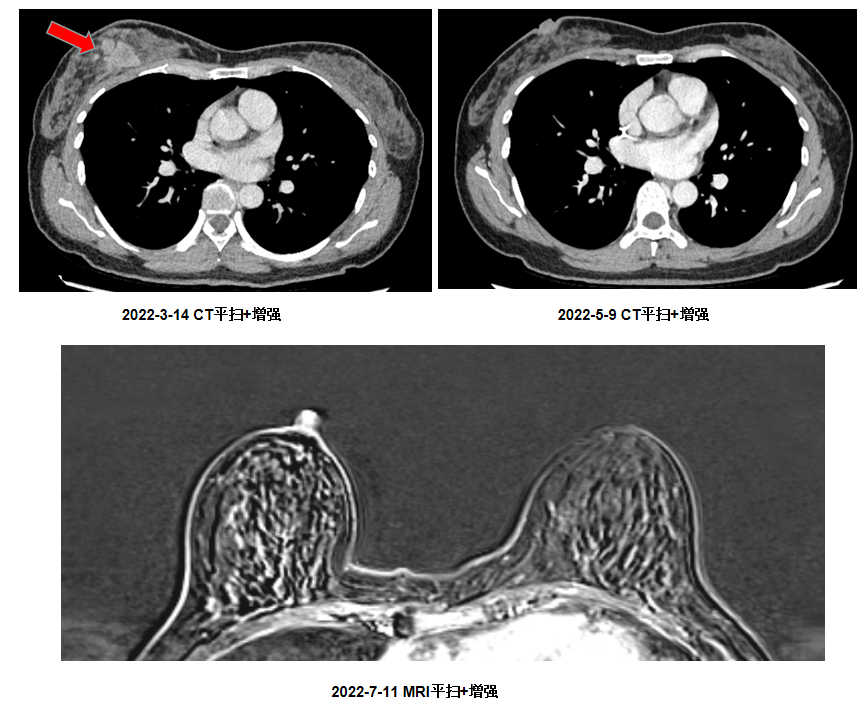

2022-3-14 CT平扫+增强提示:右乳内见一结节状软组织影,大小约2.9×2.9cm,边界毛刺、分叶。

2周期 2022-5-9 CT平扫+增强提示:右乳未见明确肿块影。

4周期 2022-6-22 CT平扫+增强提示:右乳未见明确肿块影。

6周期 2022-7-11MRI平扫+增强提示:两侧乳腺呈多腺体型,腺体组织呈斑片、斑索状、结节状信号增高影,信号不均匀,边缘模糊;DWI未见弥散受限,两侧乳腺象限未见明确肿块及异常强化征象。两乳皮肤、乳头未见异常。

治疗6周期后,2022-7-11乳腺MRI未见明显肿物,疗效评估CR。